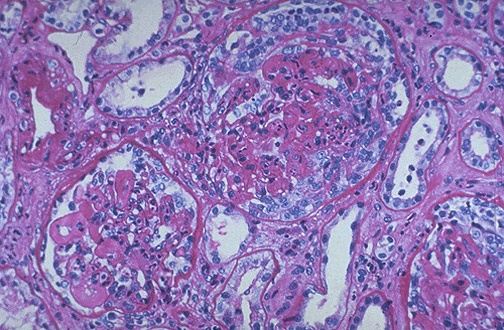

| Seen here within the glomeruli are crescents composed of proliferating epithelial cells. Crescentic glomerulonephritis is known as rapidly progressive glomerulonephritis (RPGN) because this disease is very progressive. There are several causes, and in this case is due to SLE. Note in the lower left glomerulus that the capillary loops are markedly thickened (the so-called "wire loop" lesion of lupus nephritis). |